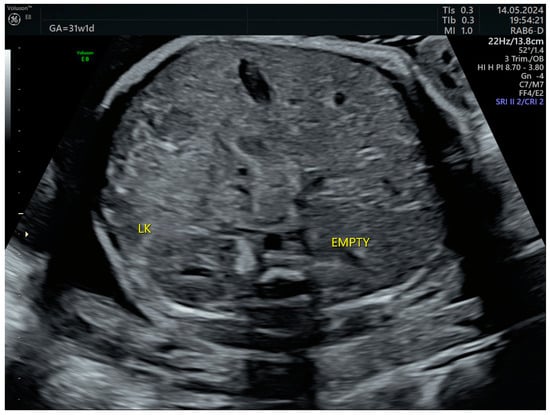

The combined test result indicated a low risk for trisomies, preeclampsia, and intrauterine growth restriction. However, during the ultrasound examination, the absence of the right renal tissue in the right parasagittal sections was noted (Figure 1). Examination of the embryo in axial sections demonstrated the presence of a relatively well-defined acoustically heterogeneous echogenic mass situated anterior to the spine, in sonographic contact with the renal tissue image correctly occupying the left lumbar fossa (Figure 2). Those aspects suggested the existence of a renal anomaly of crossed fused renal ectopia. No other embryonic anomalies were detected, the bladder image was present, and the amniotic fluid volume was normal. The calculated gestational age corresponded to the ultrasound estimate. The suspicion of crossed fused renal ectopia was maintained during a subsequent reevaluation at 17 weeks of pregnancy (Figure 3 and Figure 4).

The third-trimester ultrasound evaluation at 31 weeks and 5 days confirmed once again the presence of crossed fused renal ectopia. Although the frequency of the associated changes (hydronephrosis, calyceal dilatations, ureteral dilatations, ureterocele, oligohydramnios, vesicoureteral reflux, etc.) in the third trimester is relatively high, none of these complications were present at the time of examination (Figure 7 and Figure 8). No other anomalies or deviations from the fetal growth curve were recorded, even though, starting from the 28th week, the patient developed diet-controlled gestational diabetes. The final diagnosis was isolated crossed fused renal ectopia.

Figure 7. Right lumbar fossa without renal image—third-trimester morphology scan at 31 weeks. LK—left kidney.